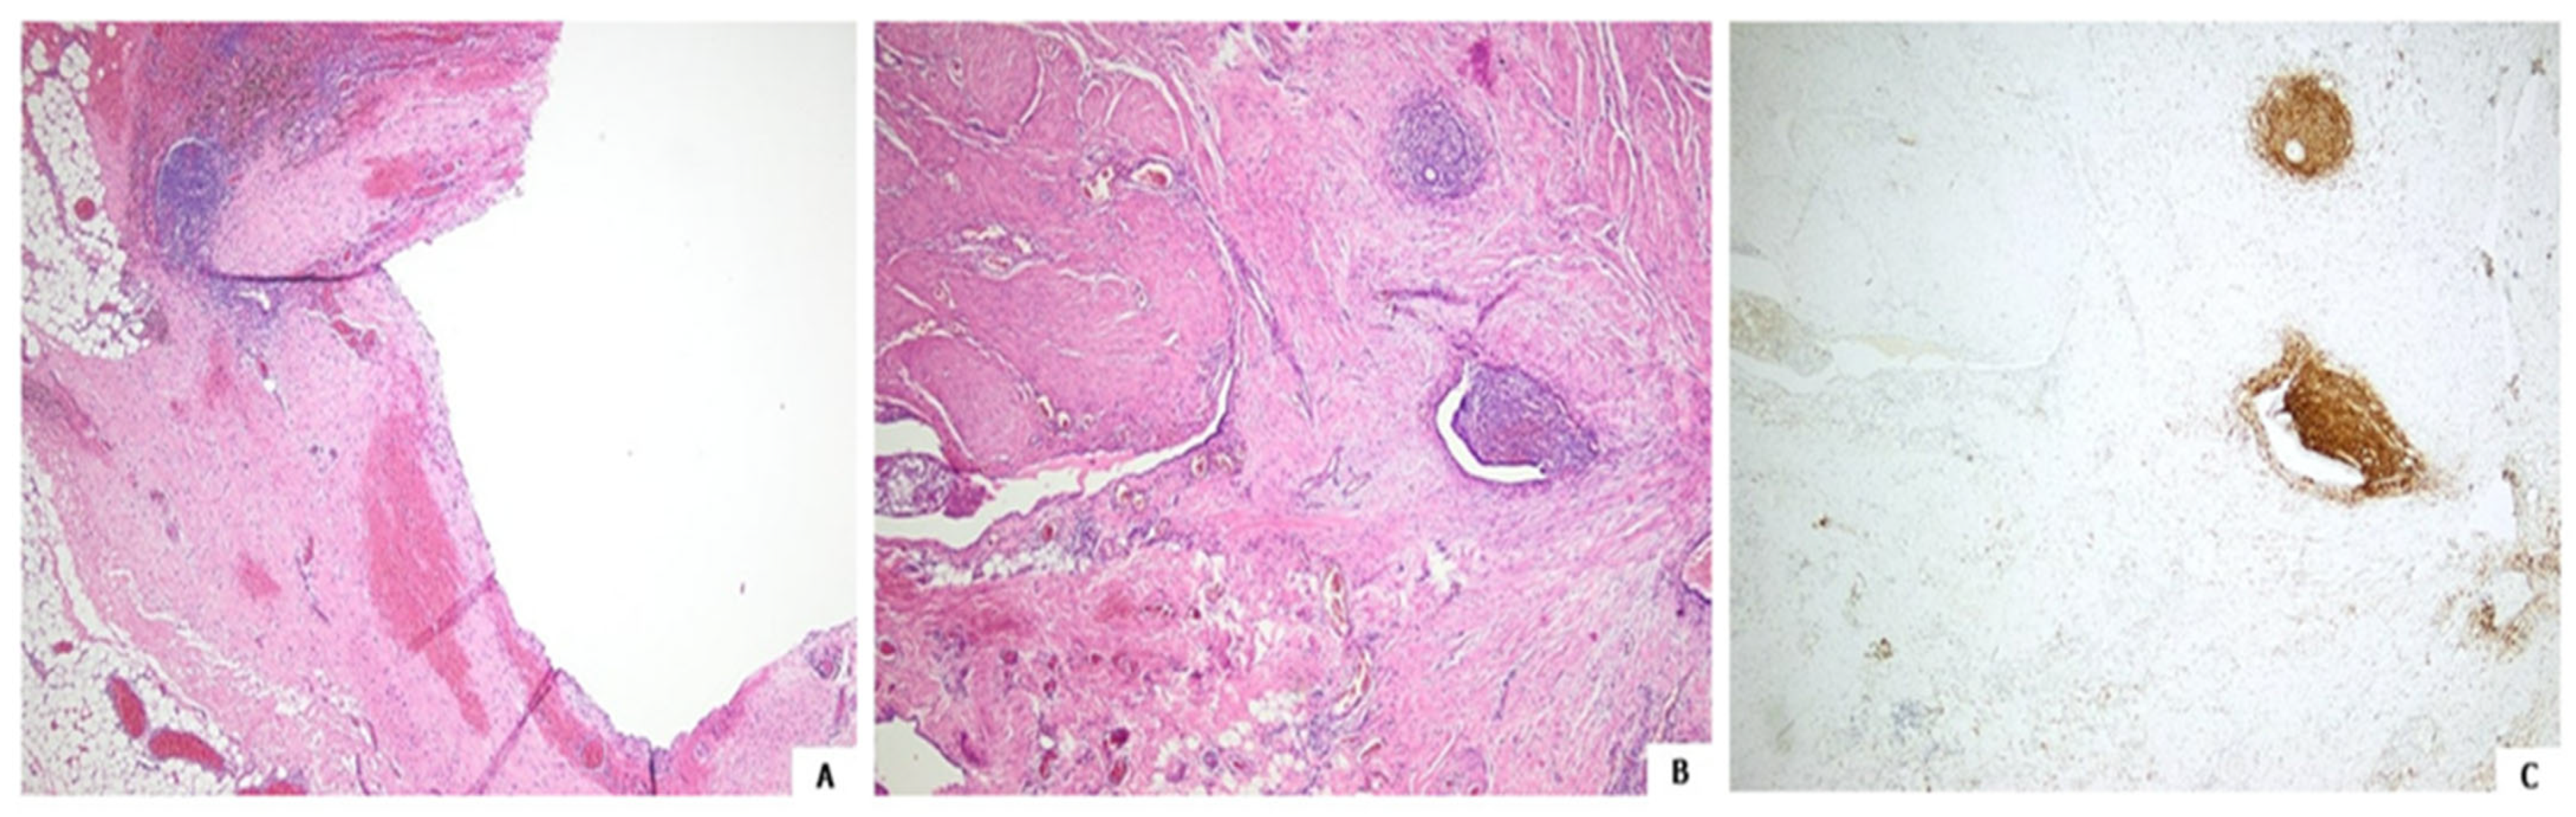

Histology after hematoxylin and eosin staining followed by immunochemistry showed the lesion to be an endometriosis focus, with both the cyst and adjacent glands focally lined with endometrial-like epithelium; CD10 immunopositive stromal cells were also seen (Figure 3) [4,5].

Figure 3. Endometriotic cyst. Attenuated epithelial lining, hemorrhage and pigmented histiocytes adjacent to endometrial stroma ((A), hematoxylin and eosin, 40×). Endometrial glands and stroma within the cystic wall ((B), hematoxylin and eosin, 40×). Endometrial stromal cells highlighted by CD10 immunoreactivity ((C), CD10 immunostain, 40×).